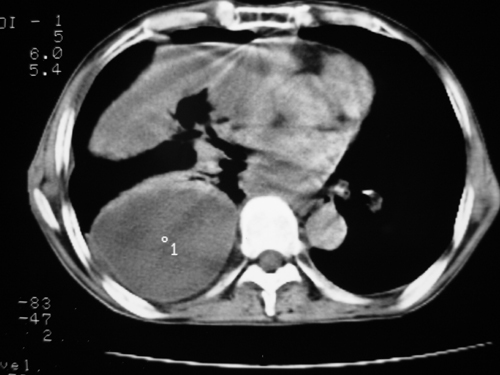

以下是引用yangyudong333在2008-4-29 5:46:00的发言:[br]1左上叶结节呈分叶状,边缘毛刺,考虑肺癌并纵隔淋巴结转移可能性大,结核待排,[br] [br]2右侧多发包裹性胸腔积液

以下是引用zsl6918在2008-4-29 9:15:00的发言:[br]右侧包裹性积液穿刺术后改变,肺内多发结节不除外转移可能。建议查胸水,问病史。